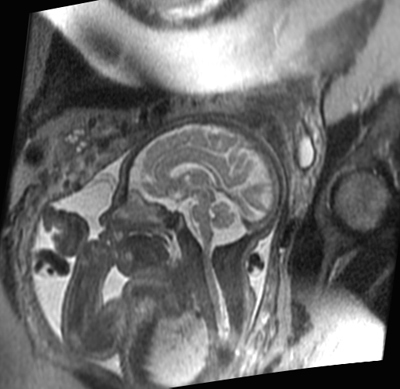

Resonancia magnética en el diagnóstico de malformaciones cerebrales del feto

En comparación con la ecografía, la RM aumentó la precisión del diagnóstico y modificó los planes de manejo. El estudio fue bien tolerado. The Lancet, 14 de diciembre de 2016